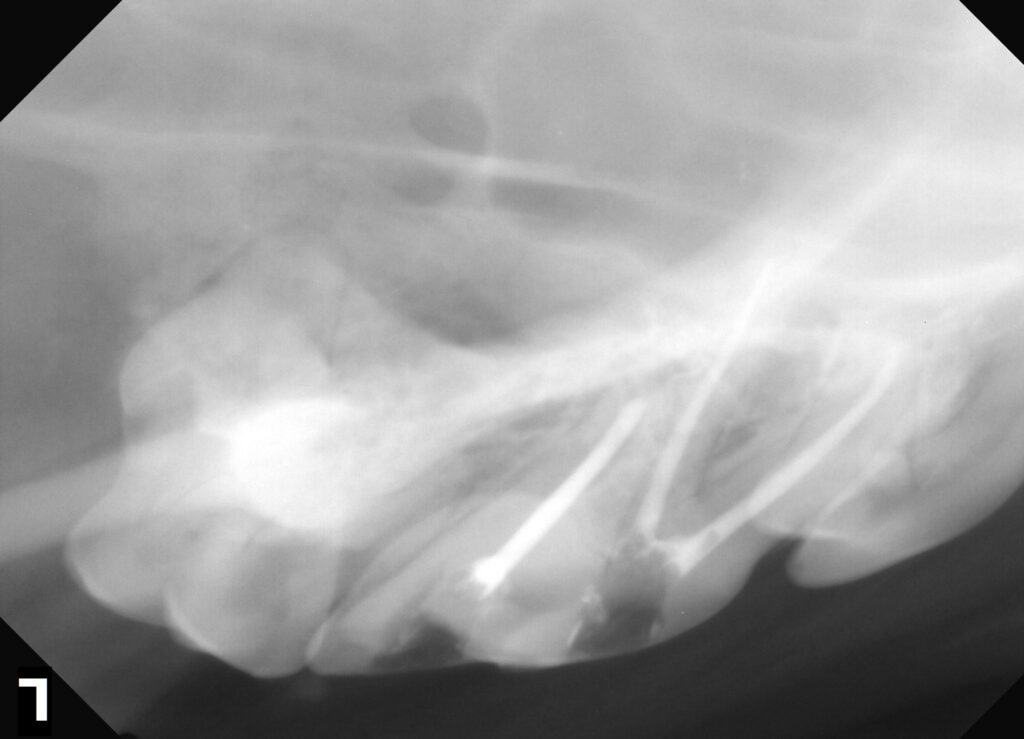

ヒヅメやアキレスなどを与えて歯が折れる子が少なくありません。

不用意に硬いおもちゃも与えないようにしましょう。

治療後